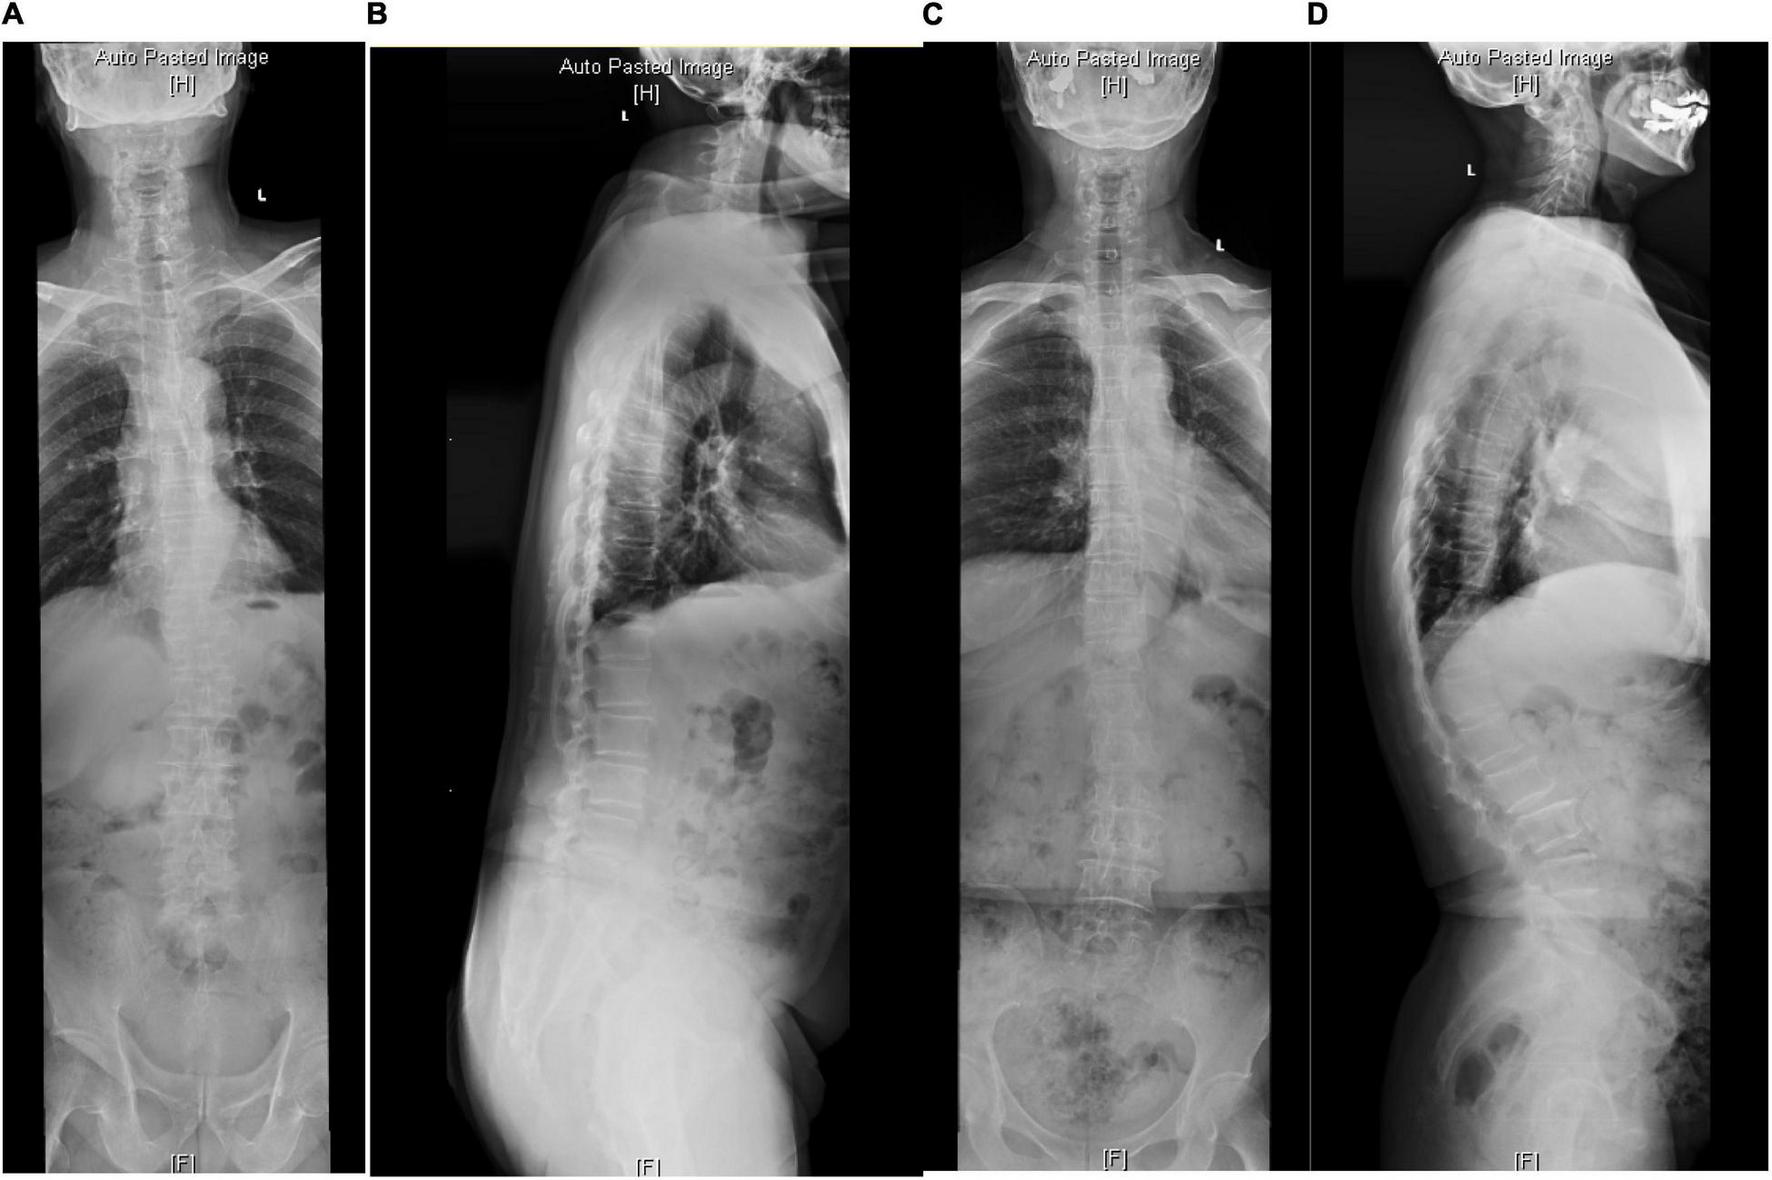

Figure 2. The radiological parameters measured on standard anterior-posterior and lateral whole spine X-ray of cases from the SIB group. (A,B) In a 68-year-old woman, TK = 16.4, TLK = 1.1, LL = 19.5, PI = 63.4, PT = 39.9. (C,D) In a 72-year-old man, TK = 40.9, TLK = 40, LL = 72.2, PI = 51.7, PT = 3.7.

In the SB group, PI-LL was negatively related to LL (r = −0.492, P < 0.001), and TK was positively related to PT (r = 0.440, P = 0.02) and LL (r = 0.370, P = 0.008). In the SIB group, PI-LL was positively correlated to PT while negatively related to TK and LL (P < 0.01). LL was correlated to PT (P = 0.037) and TK (P < 0.001) (Table 3 and Figures 1, 2).